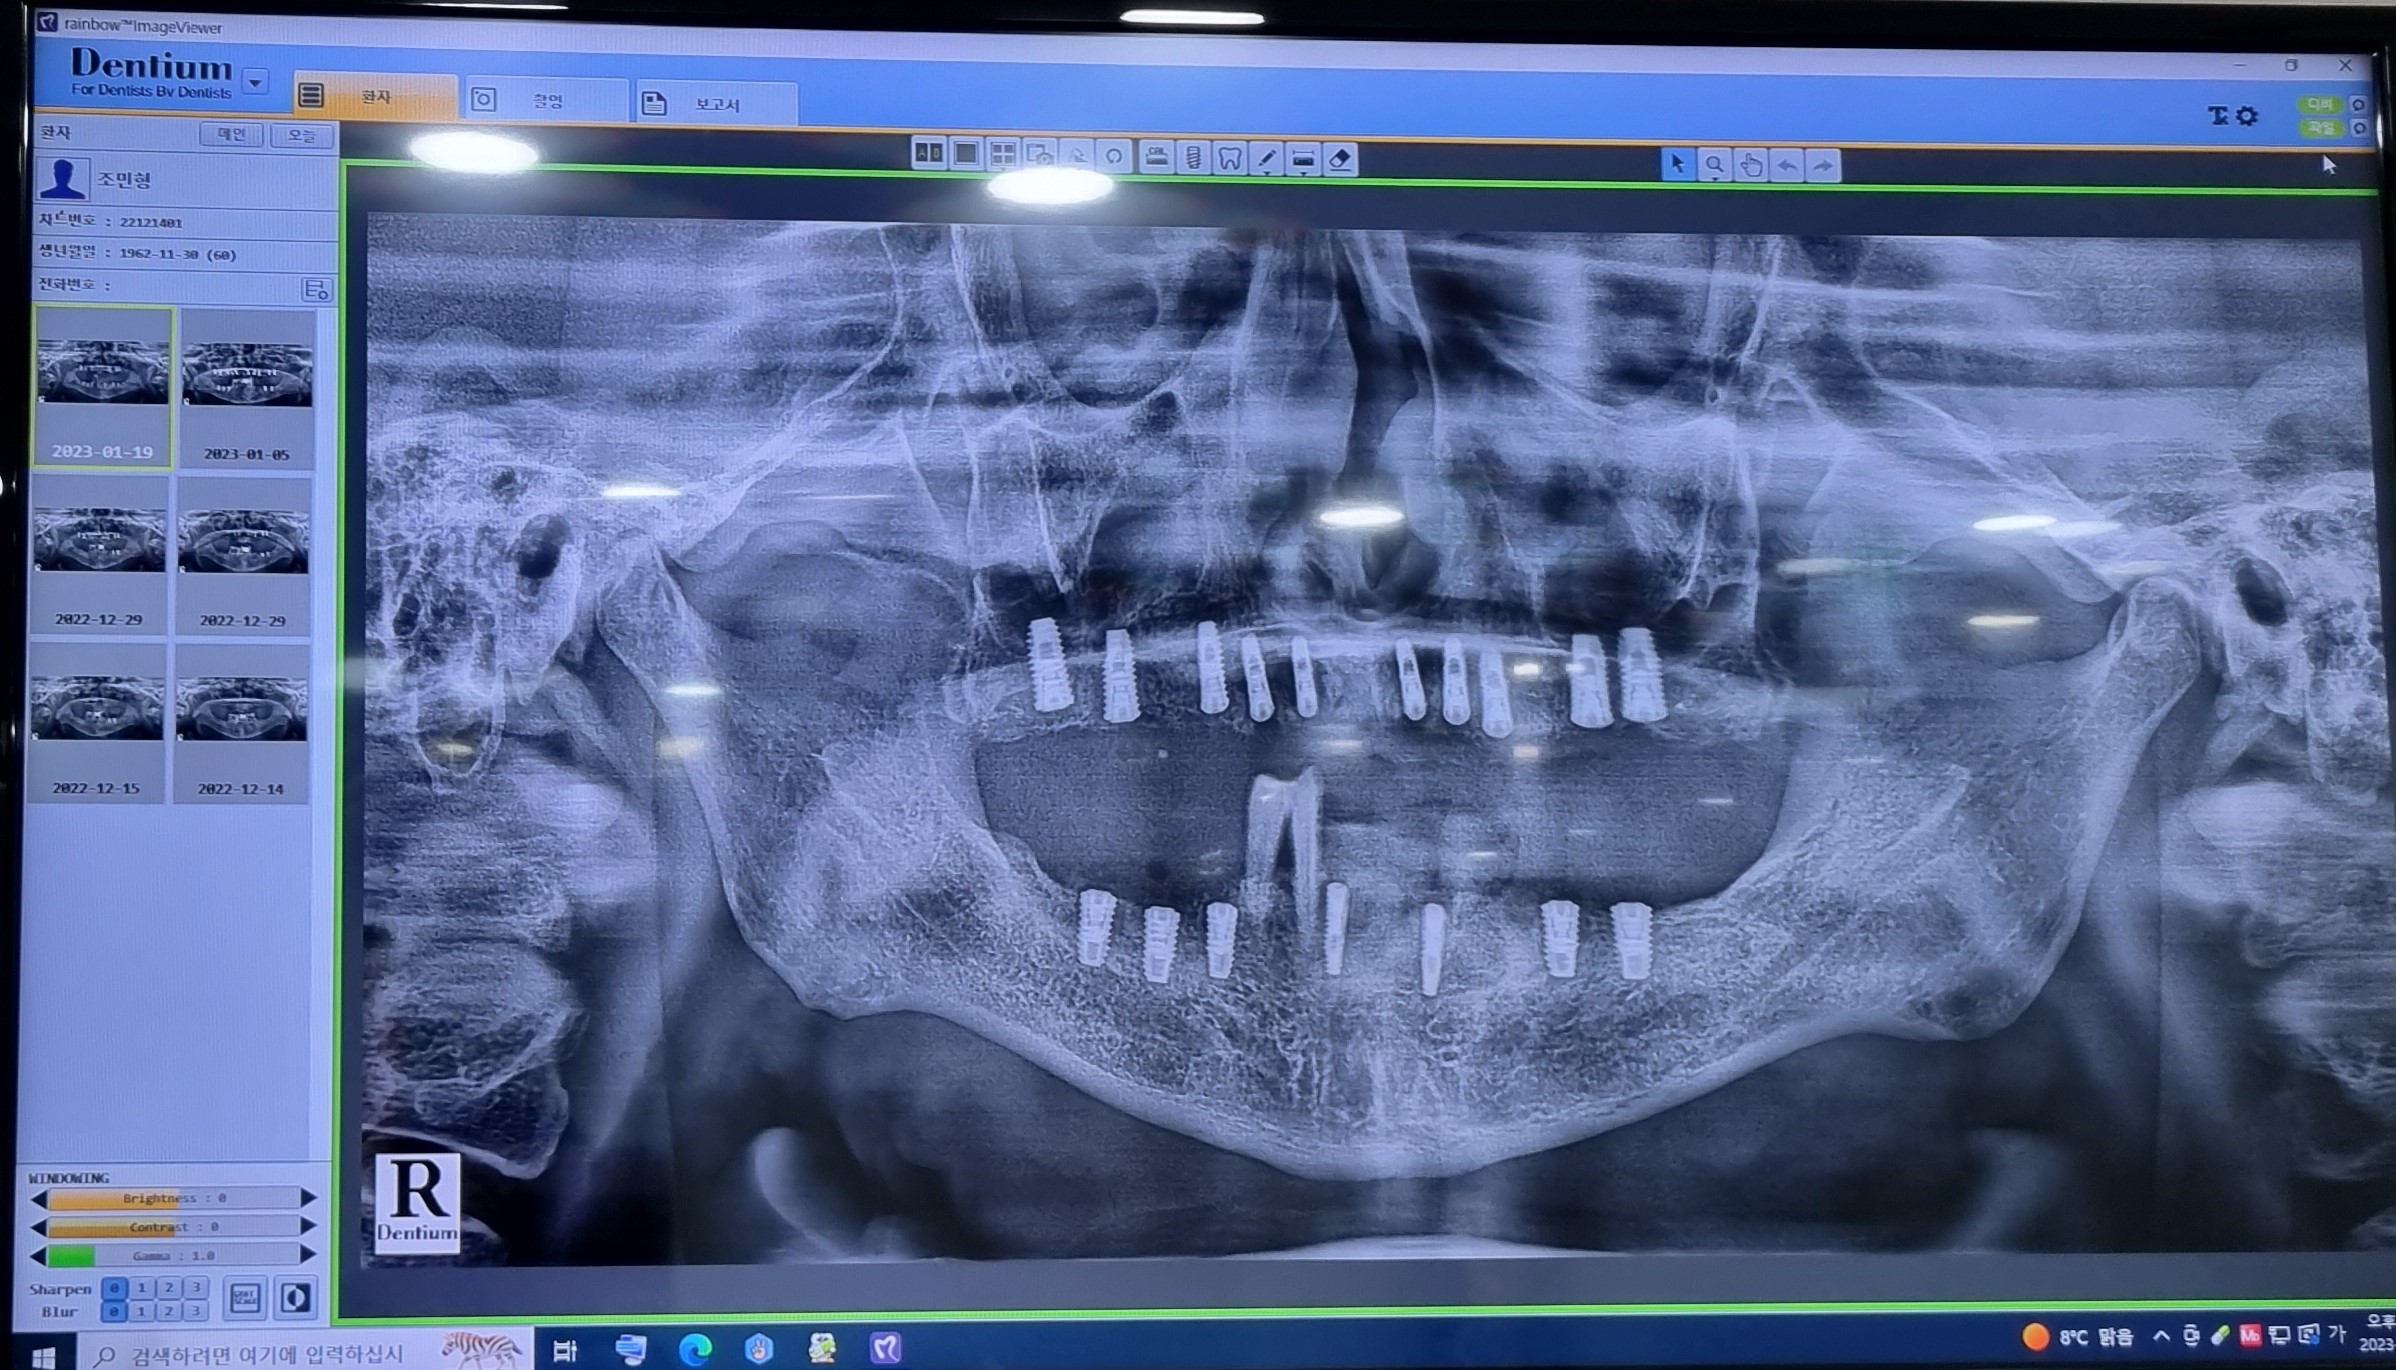

2022 1229

1차 윗니 상악上顎동 거상술

오늘은 윗니上顎 우축 14.16.17 치조골이식술을  동반한  인공치아  식립植粒술이 진행하였습니다.

잇몸을  절개하여  임몸뼈에  임플란트dental implant의  뿌리  부분인  픽스쳐Fixture를

식립植粒하는  수술입니다.

이제  윗니上顎 10X-ray 이미지에서도 모두 1차  수술  치료가  깔끔하게  긑낫습니다.

202315

1차  아랫니下顎 우축 1개을  발치와 45.48.47뼈이식 3개의 임플란트dental implant식립植粒 수술을  하였습니다

수술은  20분  정도가  걸렸습니다

상학上顎  1차수술 7개의  실밥을  모두 제거  햇습니다

2023119

1차 임플란트dental implant시술

아랫니下顎  앞니 브릿지1개를  포함하여 32.33.41.42 4개의 치아를  쪼로록록  발치拔齒와  33.42 .

임플란트dental implant 2개 식립植粒 하는  수술이 완료  되었습니다